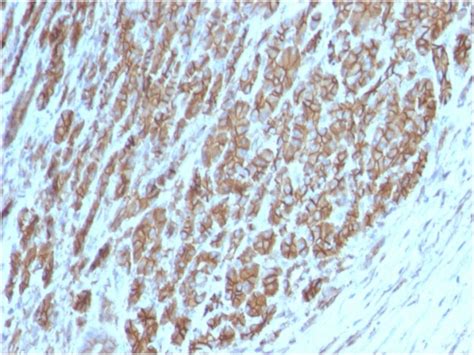

p120 expression in invasive breast cancer metas...

Cytoplasmic and nuclear localization of p120 in...

P120 protein expression | Download Scientific D...